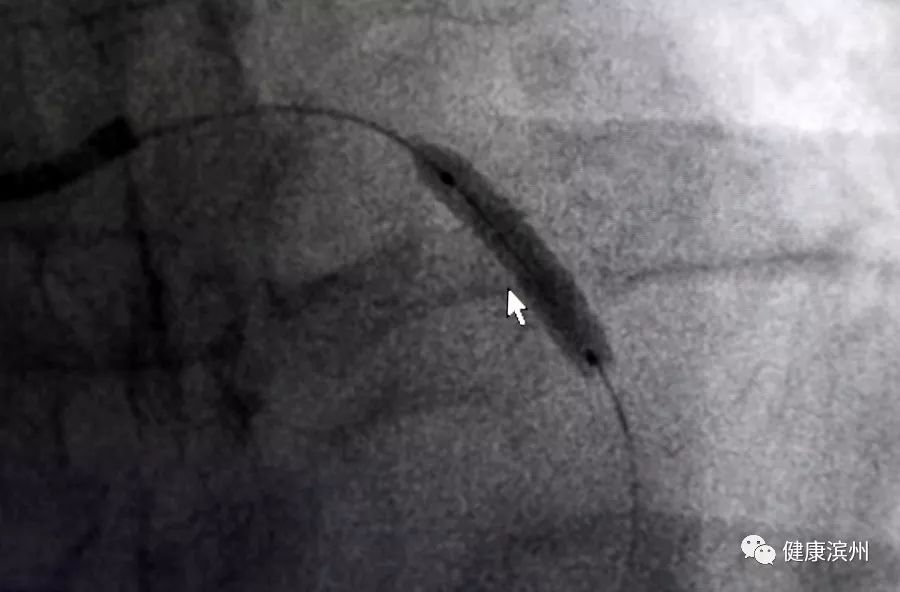

術中,心臟支架放入。